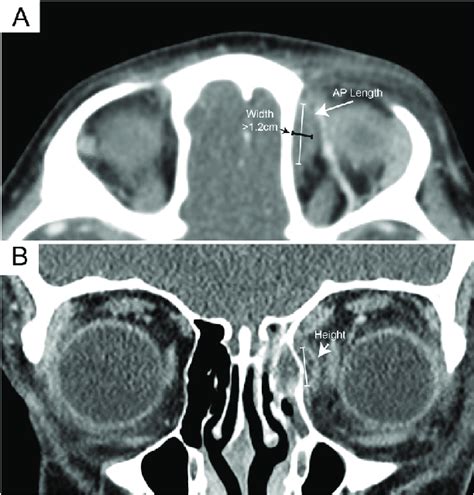

Understand the progression of orbital cellulitis stages, from early symptoms to severe complications. Learn how to identify warning signs, the importance of prompt diagnosis, and effective treatment options like antibiotics or surgery. Protect your vision by recognizing the critical differences between preseptal and orbital infections in this comprehensive guide to managing eye health risks.

Read full article: Orbital Cellulitis Stages